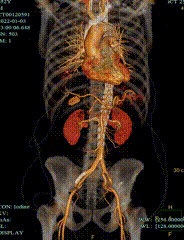

夹层近端封闭良好。夹层动脉瘤累及整个内脏区动脉,腹腔干、肠系膜上动脉假腔供血,腹腔干开口重度狭窄;右肾动脉真假腔供血,以假腔为主;左肾动脉真腔供血。肾下腹主动脉段无裂口,右侧髂外动脉存在裂口。

CT影像